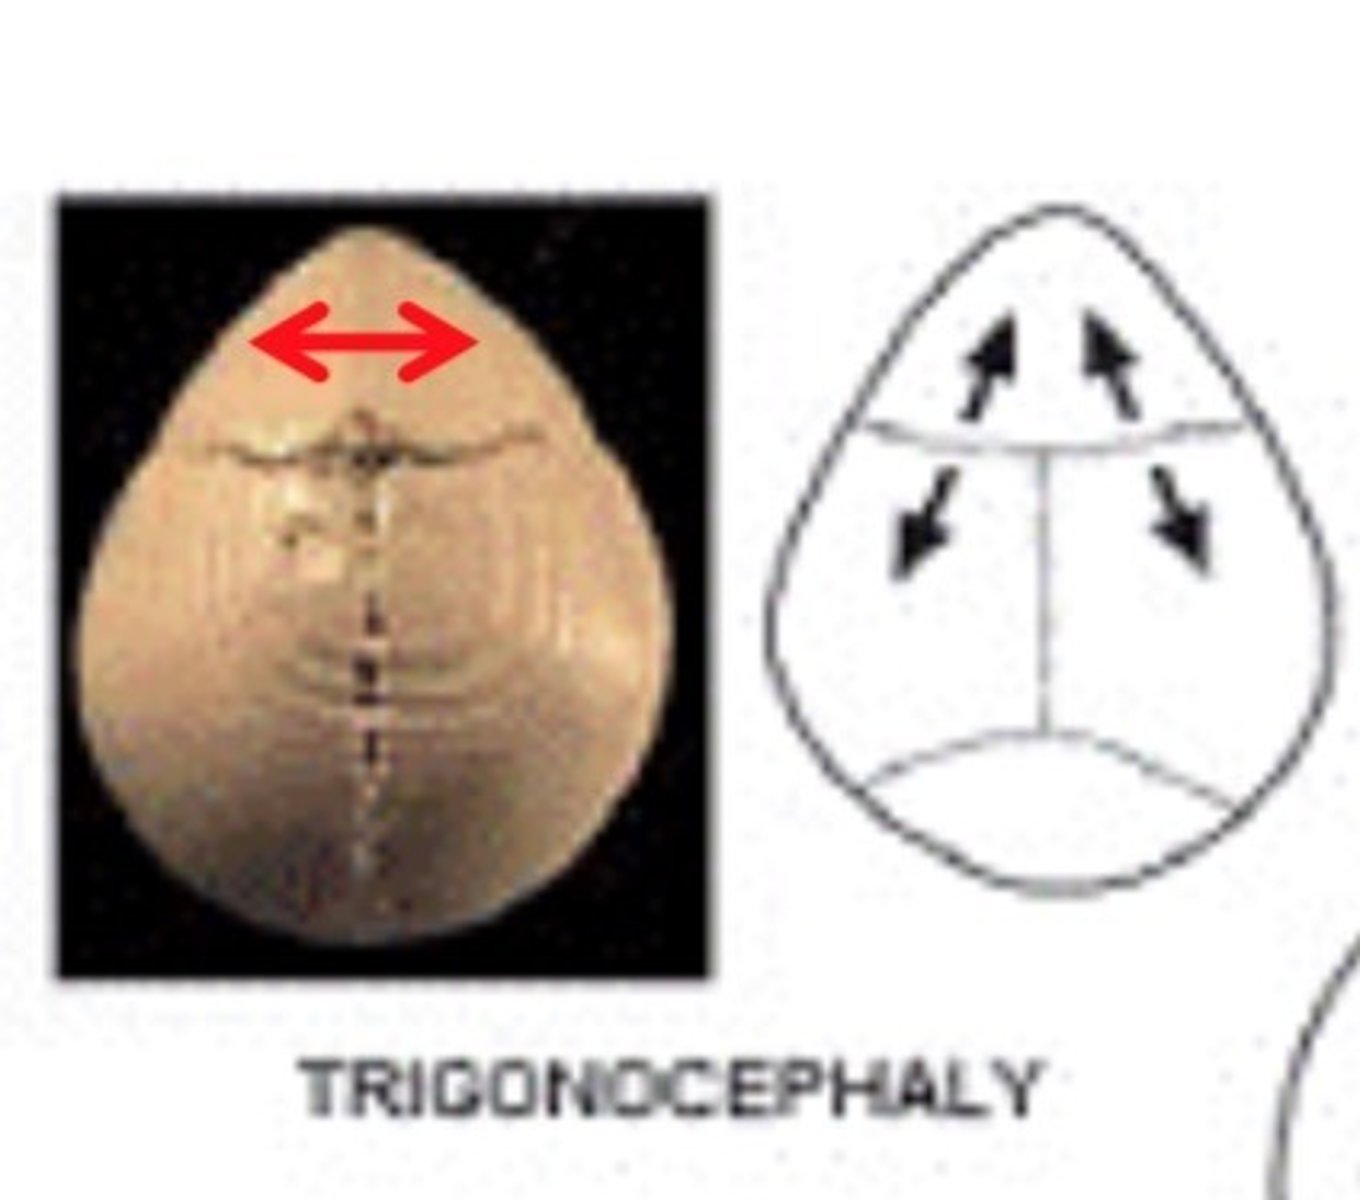

metopic craniosynostosis

fusion of the frontal suture resulting in elongation at the forehead